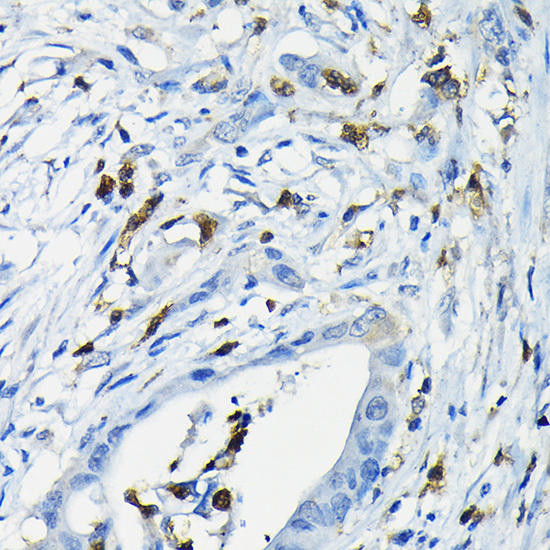

// system_update_altDatasheetsystem_update_altMSDSAnti-GPAM Antibody (CAB6610)The GPAM Polyclonal Antibody (CAB6610) is a valuable tool for researchers studying GPAM, an enzyme involved in lipid metabolism and energy production. This antibody, generated...